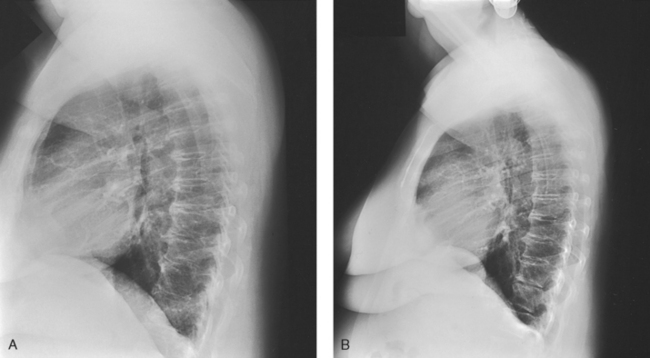

For radiography of the heart and lungs, the patient is placed in an upright position whenever possible to prevent engorgement of the pulmonary vessels and to allow gravity to depress the diaphragm. Of equal importance, the upright position shows air and fluid levels. In the recumbent position, gravitational force causes the abdominal viscera and diaphragm to move superiorly; it compresses the thoracic viscera, which prevents full expansion of the lungs. Although the difference in diaphragm movement is not great in hyposthenic individuals, it is marked in hypersthenic individuals. Figs. 10-10 and 10-11 illustrate the effect of body position in the same patient. The left lateral chest position (Fig. 10-12) is most commonly employed because it places the heart closer to the IR, resulting in a less magnified heart image. Left and right lateral chest images are compared in Figs. 10-12 and 10-13.

Fig. 10-18 A, Lateral chest radiograph performed at 44-inch (112-cm) SID. B, Radiograph in the same patient performed at 72-inch (183-cm) SID. Note decreased magnification and greater recorded detail of lung structures.